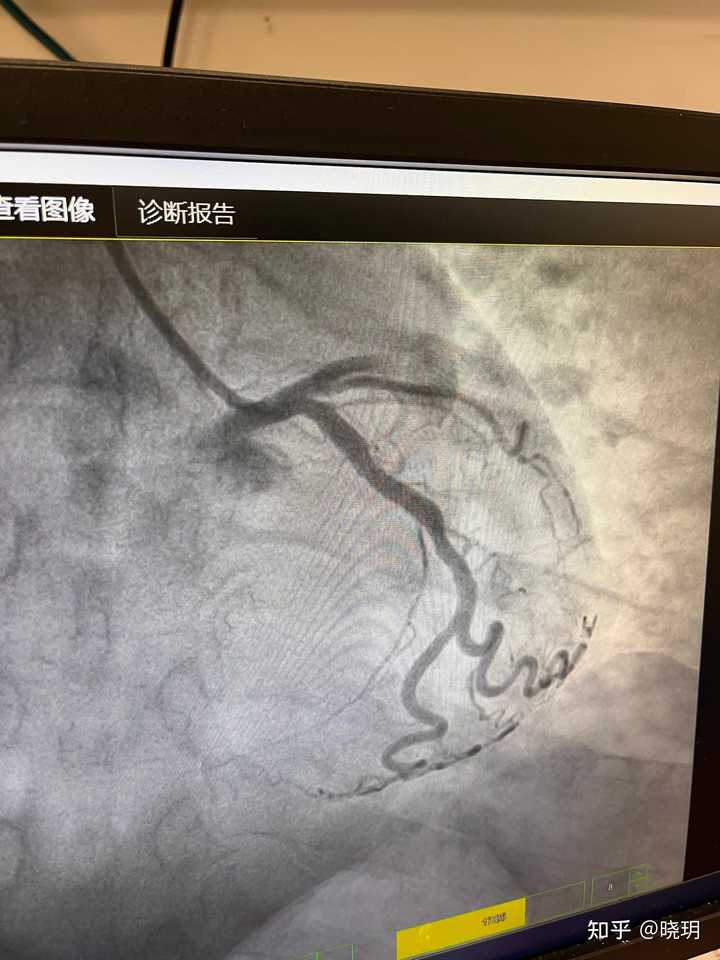

医院不让拍照,我就放一张照片吧

是前降支,xx支,xx支。其中一根堵99%下了1个支架,另外2根堵60-70%,不做处理。

造影堵了三根血管,其中主动脉堵了99%,两根支动脉堵了70%,也没等我媳妇儿来签字就直接下了一个支架。